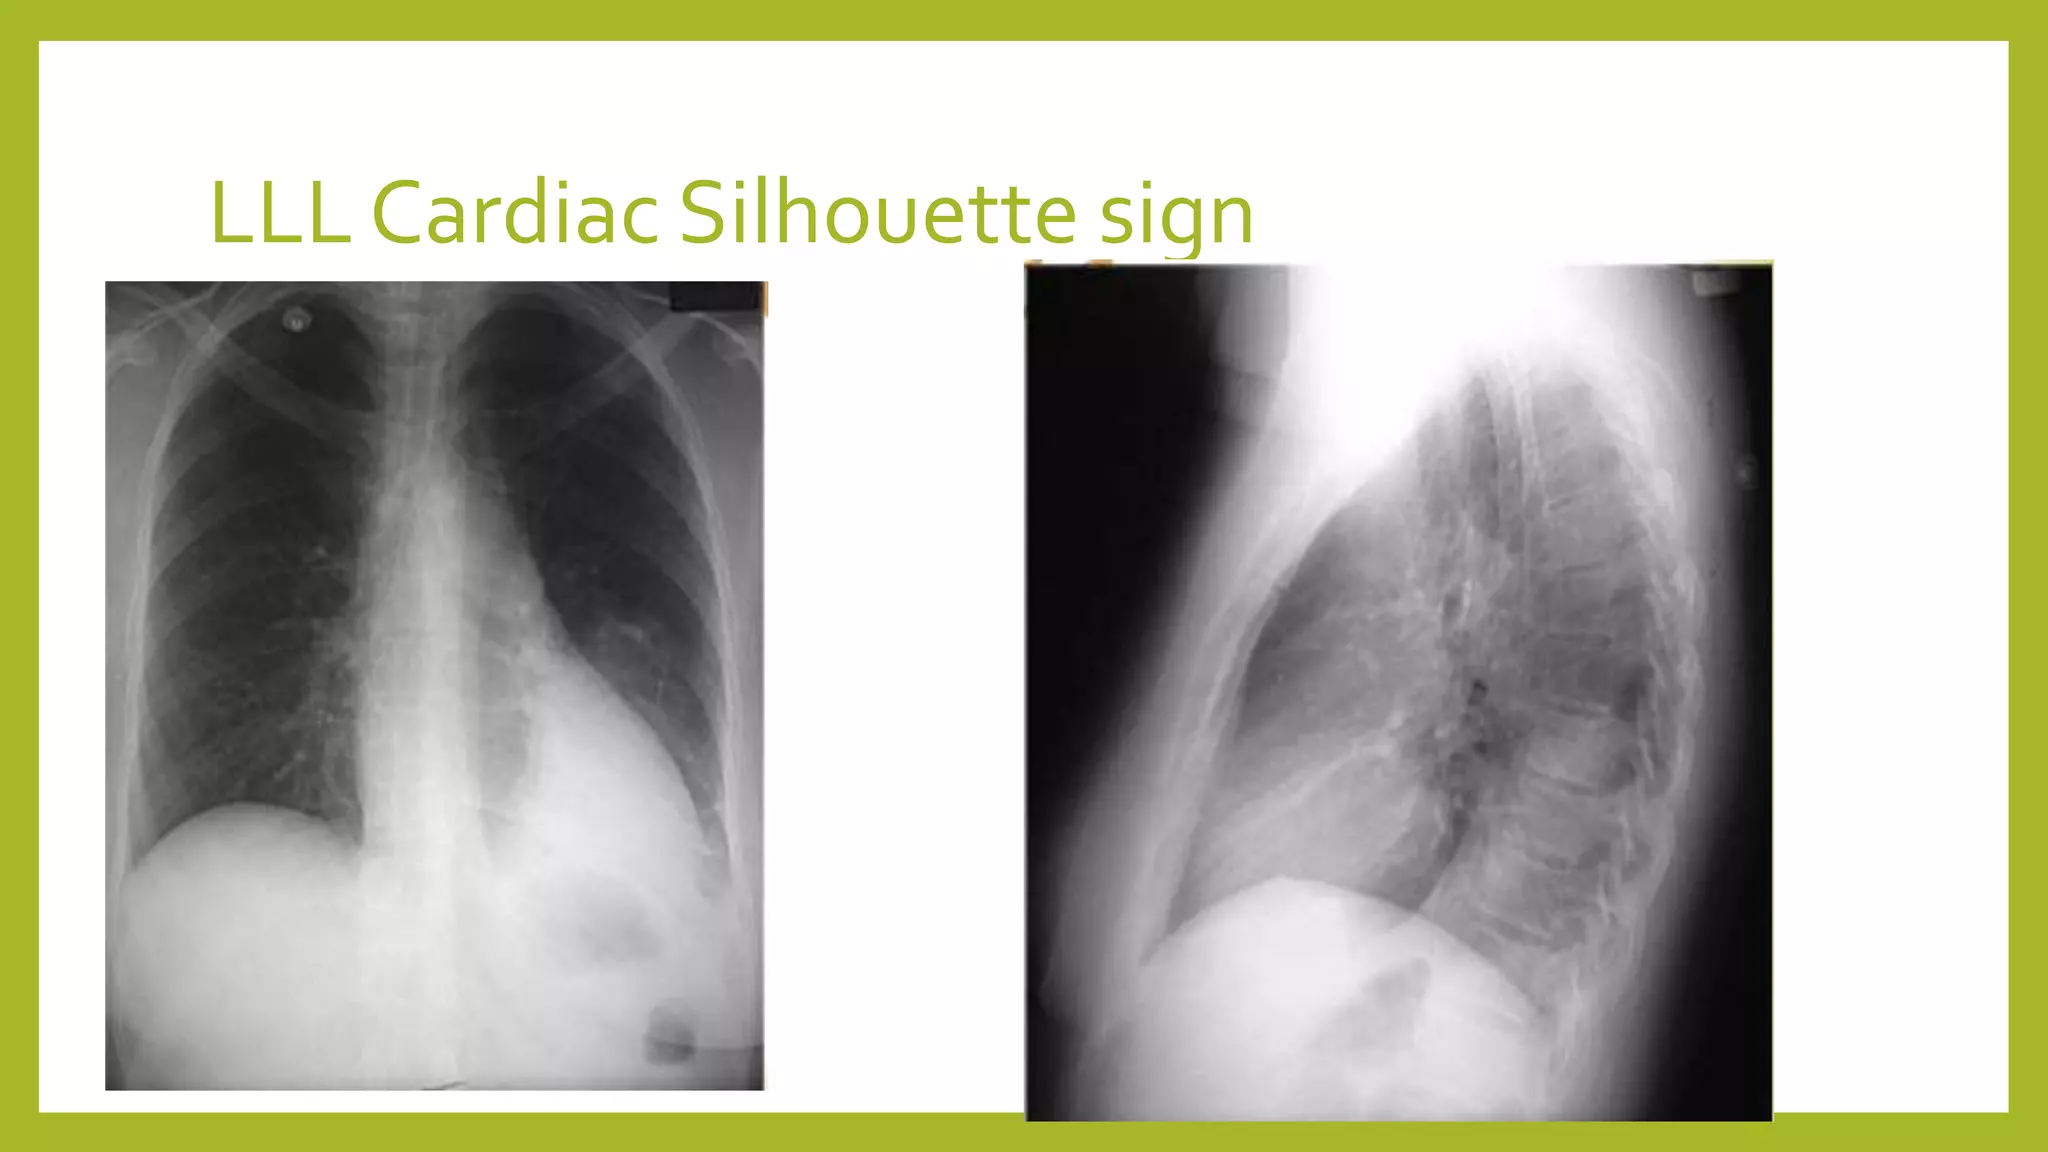

The document provides guidance on approaching and interpreting chest x-rays (CXR). It outlines steps to check the name, date and quality of the film, systematically scan the CXR looking for abnormalities, and determine if the lungs appear too white or black. Specific signs are described to help localize abnormalities, including the cardiac silhouette sign and pleural effusion signs. Examples are given of respiratory distress syndrome, tetralogy of fallot, transposition of great arteries, and total anomalous pulmonary venous return. The take home message is to summarize positive findings, compare to prior CXRs if available, and confirm findings with a radiologist.